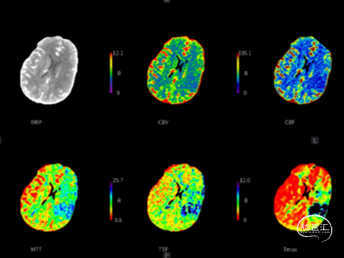

术前CTA+CTP:术前CTA可见左侧后交通动脉开放,左侧颈内动脉末端、大脑前动脉和大脑中动脉显影,左侧颈内动脉C6近端、大脑中动脉M1远端未显影。左侧颈内动脉区域CBF下降,CBV大致正常,MTT、TTP延长。

左右滑动查看更多